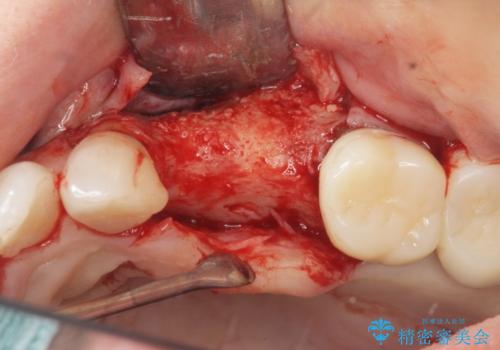

- グラグラする小臼歯の治療、全体的な治療のやりかえを希望され来院されました。

歯の穿孔(内部穴が開いている状態)破折等、歯を保存することができない問題が小臼歯には認められたので抜去を行います。

抜去後の補綴治療は長いブリッジではなくインプラント治療を希望されましたが、穿孔・破折による周囲の骨吸収をリカバリーすべく骨の造成を伴うインプラント治療を計画します。

インプラント治療を行うにはインプラント周囲に十分な骨の幅・高さが必要です。

今回はが原因で失われてしまった骨の幅を回復することで長期的な予後を見込めるインプラント治療を行うことができました。